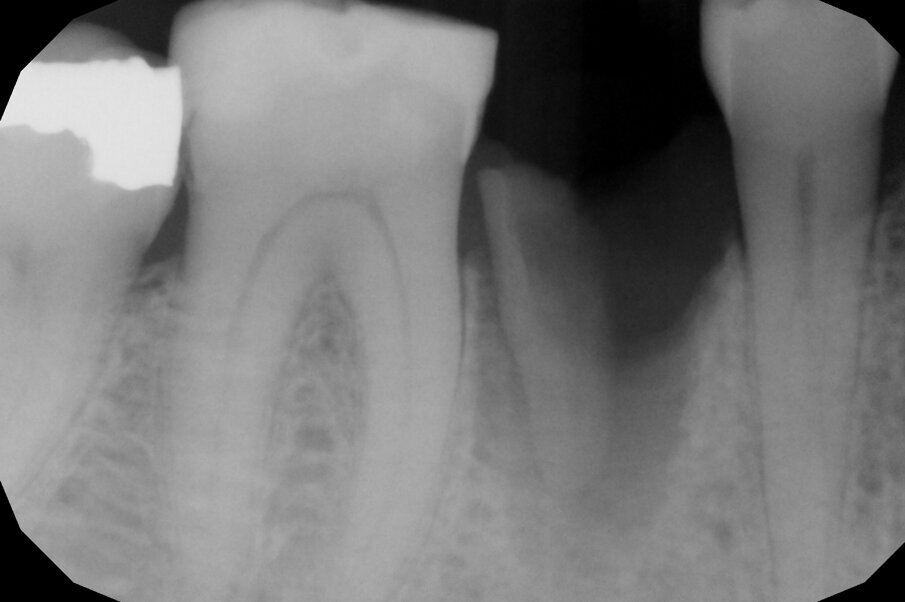

In questo caso clinico la difficoltà consisteva nel fatto che si è resa necessaria l’estrazione della metà mesiale della radice fratturata e quindi nel far compiere al frammento radicolare rimasto un movimento diagonale per mezzo del quale la porzione distale rimasta con il legamento parodontale avrebbe permesso una corretta rigenerazione tissutale ossea come indicato in rosso nell’immagine radiografica.

Per ottenere questo risultato nel gennaio 2021 è stato ancorato un segmento di arco in acciaio a sezione quadrata 0.021” x 0.025” agli elementi 4.4 e 4.6 per mezzo di composito. Il segmento è servito da ancoraggio per una molla con forza di trazione 150 g in posizione obliqua in senso disto-mesiale.